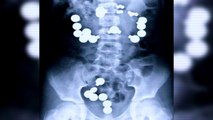

10 Craziest Things Found In Peoples Bodies

From an engagement ring to a 10 pound hairball, we take a look at the 10 craziest things found in peoples bodies. Subscribe (new video every day!)